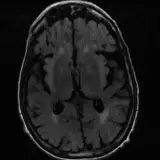

Over 2,100 interactive radiology cases, curated by radiologists for your level of training. Scroll, window, and view cases full screen — just like on PACS. Click linked findings in each writeup to jump straight to them on the image. Cases include sample reports, a focused discussion section, original illustrations, and videos.

Casos totalmente interactivos con las herramientas que esperaría de un PACS: scroll, ventana, zoom, pan, mediciones, ROI y modo de pantalla completa.

• Anotaciones enlazadas

Anotaciones extensas resaltan los hallazgos clave directamente sobre los casos. Haga clic en los hallazgos enlazados dentro de la descripción del caso para saltar a su ubicación exacta en el estudio.

Aprenda con eficiencia gracias a hallazgos de imagen anotados e ilustraciones